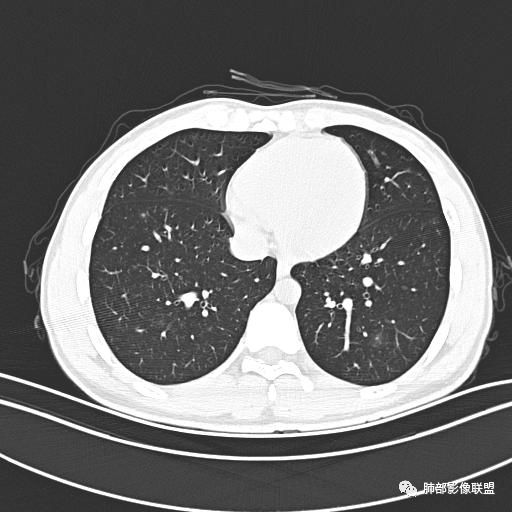

小强:青年,发热,皮疹;双肺散在结节,周围磨玻璃,点晕征,疱疹病毒感染,鉴别荚膜组织胞浆菌,结核。 大雄:青年,急性起病,发热伴全身皮疹2天,抗病毒治疗体温有下降。双肺随机分布大小不等类圆结节,“点晕征”。考虑水痘-疱疹病毒(VZV)血播询问接触史,查体皮疹分布以及形态基本可诊断。 王开金江津中心医院呼吸科:青年男性,起病急,病程短,以发热,皮疹为首发症状,感染指标以单核细胞升高为主,胸部ct双肺多发结界,周围有晕,点晕表现,随机分布,同意於老师意见,水痘疱疹病毒血流感染累及肺。 王秀仙:双肺多发大小不等结节,周围有晕,边缘模糊,呈点晕征表现。青年,急性起病,发热伴全身皮疹2天,抗病毒治疗体温有下降。考虑疱疹病毒。鉴别荚膜组织胞浆菌。 傅昌瑜:19岁男性,发热、全身皮疹2天,单核细胞增高,双肺多发结节,结节边缘见边界不清磨玻璃影。点晕征+发热、全身皮疹+单核细胞增高——考虑水痘-带状疱疹病毒肺炎。 一切∮随缘:年轻男性,发热,皮疹两天,实验室,CRP,PCT增高,影像:双肺多发散在磨玻璃结节,边界欠清,大小不等,呈点晕征改变,以血管束周围分布为主,局部血管束略增粗,其它无明显改变,考虑:1:病毒性肺炎(水痘疱疹病毒?不知道皮肤有无改变)2:真菌(组织胞浆菌,血管侵袭性肺曲霉)3:GPA4:寄生虫(实验室没有看到嗜酸细胞增高) 赵山河:双肺散在结节,周围有晕,边缘模糊,呈点晕征表现。青年,急性起病,发热伴全身皮疹2天,抗病毒治疗体温有下降。考虑水痘—疱疹病毒感染。洪桥爱:青年男性,发热、皮疹2天,伴瘙痒,皮疹于面部首发,之后进展至全身,虽然没有对皮疹进行描述,但是从出疹时间及皮疹进展情况,伴瘙痒,应该就是个水痘患者;CT提示双肺随机分布结节影,部分结节伴有边界不清晕征,考虑水痘血播肺。 刘强:年轻男性,急性起病,皮疹,发热,抗感染治疗体温下降,说明有效。影像表现为散在点晕征,感染类疾病谱(疱疹病毒,真菌,结核),结合年龄,皮肤皮疹,考虑水痘-疱疹病毒性肺炎。 小兜:男性,19岁,发热皮疹两天,颜面部至全身,CRP,降钙素及单核增高。CT示双肺散在小结节,周围伴磨玻璃影,点晕征,考虑为水痘-带状疱疹病毒(varicella-zoster virus,VZV)肺炎 必有路:青年,皮疹+发热+“点晕征”→水痘-疱疹病毒(VZV) 许慧良:青年男性患者,发热、皮疹2天,体温最高38.5℃,第3天皮疹扩展至全身,伴瘙痒,胸部CT:双肺多发随机分布的小结节,结节周边见边界模糊的晕征,考虑水痘病毒感染流心明智:男,19,急性起病,发热伴全身皮疹2天。出疹顺序头→全身,抗病毒有效。胸部CT:两肺多发大小不等类圆形实性小结节影,随机分布,结节周围环绕GGO,边界模糊,呈点晕征。出疹特点是关键,未提示。考虑:血播病毒性肺炎,水痘-疱疹病毒?麻疹?鉴别荚膜组织胞浆菌、TB、血管炎、寄生虫等。 浪迹天涯:病灶多为5-10mm大小结节,结节周围可见磨玻璃样的晕环,常多发,可分布于肺内任何区域,考虑水痘—带状疱疹病肺炎如果短时间内有新的一个区域浸润,更加能说明,